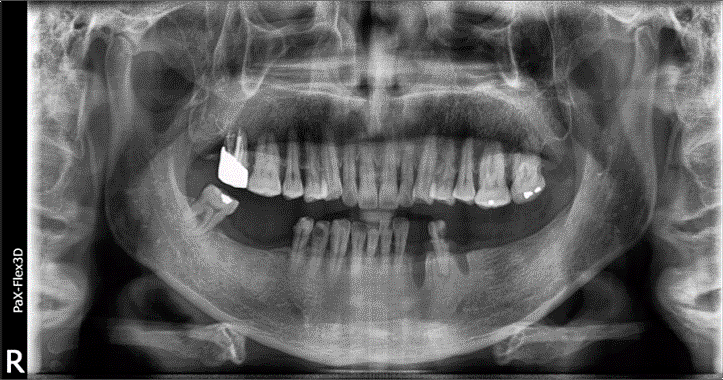

상기 환자분은 68세 남자분으로 임플란트 건강보험 적용 대상으로 본원에 치료를 위해 내원하셨습니다.

오른쪽 아래 어금니인 # 46, 47 어금니 2개 보험 임플란트 진행하셨고요. (사진상 왼쪽)

왼쪽 아래 치아도 상당 부분 상실하셨지만, 보철을 새로 해야 하는 상태셨기 때문에 다른 치아들까지 저희 병원에서 치료받으시기로 결정하셨습니다.

68세 남성

(전) 2021-11-05, (후) 2022-08-26

먼저 # 46, 47은 임플란트가 단단히 고정될 만큼 뼈가 충분해서 별도의 뼈이식 없이 치료를 도와드렸고요.

3개월 정도 임플란트 픽스처가 잘 고정되었는지 확인 후 최종 보철물을 올려 보험임플란트 시술을 마칠 수 있었습니다.

그리고 왼쪽 아래 비어있는 # 33 치아는 임플란트를 진행했고요. # 34 치아는 크라운을 씌워 정상적인 기능을 할 수 있도록 해드렸습니다.

또한 # 35, 37 치아에 임플란트를 식립하고, 가운데 # 36 치아 자리는 임플란트 폰틱(아래사진 참고)이라고 해서 브릿지처럼 중간을 연결하는 가짜 치아로 시술해 드렸습니다.

총 치료 기간은 약 9개월 정도가 소요되었고요.

전후 사진을 보시면 상당 부분 비어있던 공간에 치아가 생기면서 음식 섭취 등의 기능적인 측면뿐만 아니라 심미적인 측면에서도 훨씬 더 개선된 모습을 확인하실 수 있습니다. ^^

치료를 마치고 난 후 훨씬 더 건강하고 젊어 보이는 모습에 환자분뿐만 아니라 저희 치료진 모두가 만족도가 높았던 사례입니다.